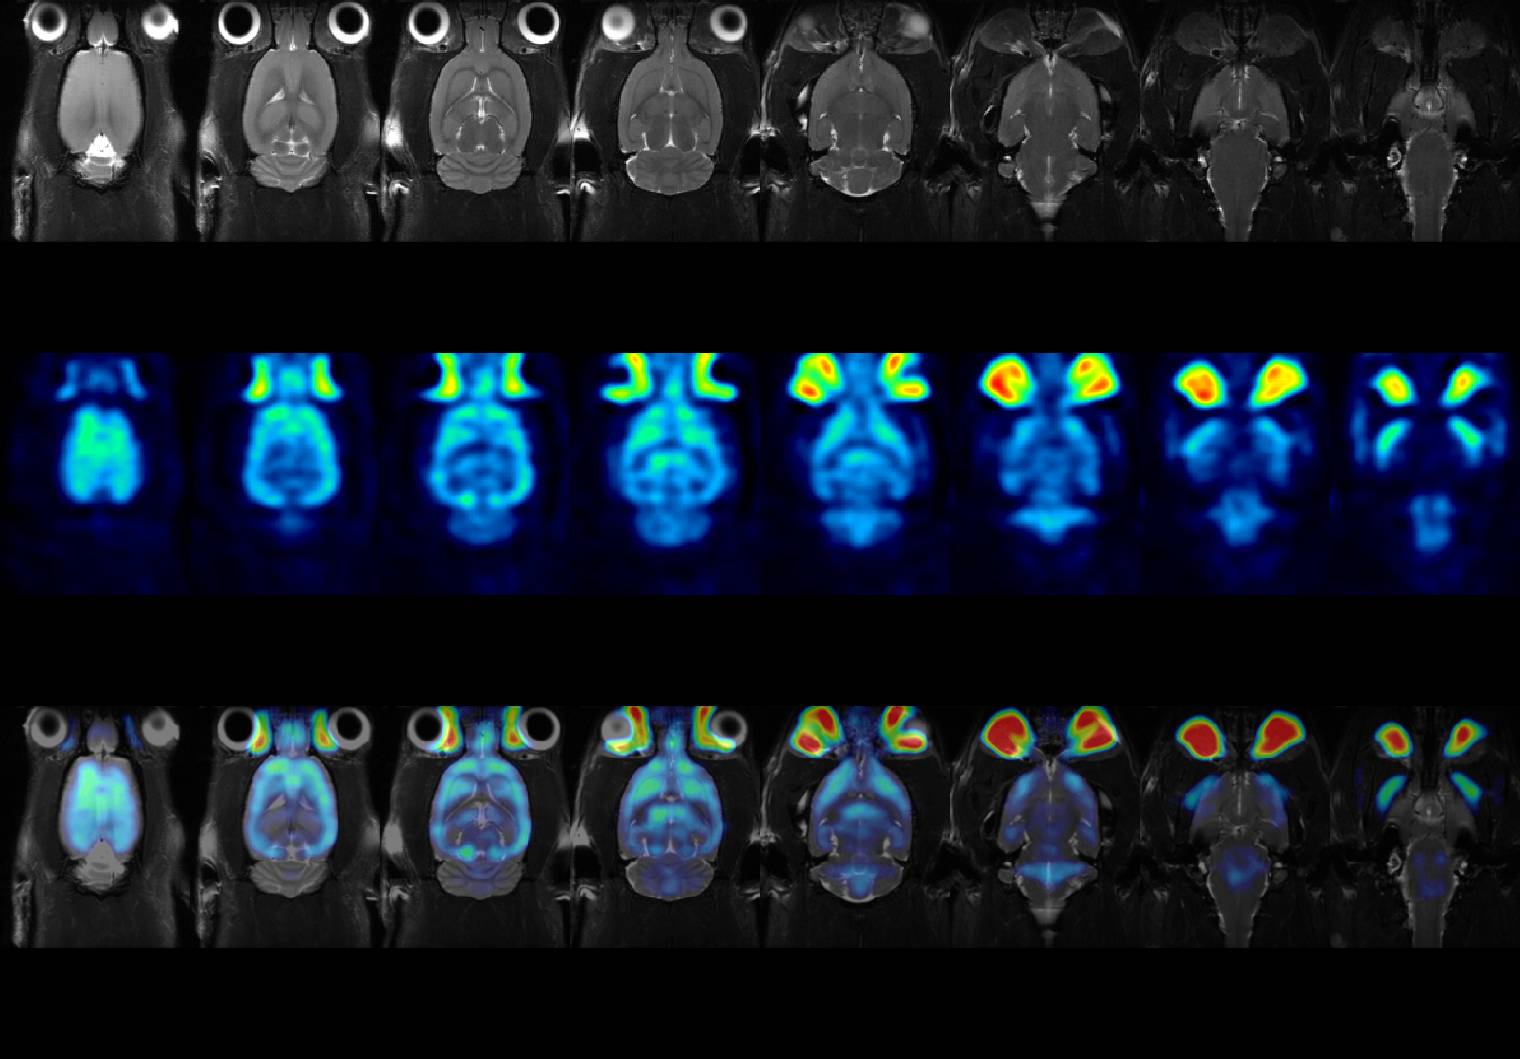

Discover the advanced imaging capabilities at the Fralin Biomedical Research Institute at VTC, part of Virginia Tech (Roanoke, VA, USA), where cancer scientists are revolutionizing preclinical research with the help of Bruker's cutting-edge technology.  The institute’s small animal imaging core features the simultaneous PET/MRI (BioSpec 94/20 + PET Insert Si 103) and PET/CT Si78, enabling researchers to monitor brain and cardiovascular dynamics with exceptional spatial and temporal resolution, non-invasively and over time.

Through insights from Michael Friedlander, Ph.D, Jenny Munson, Ph.D, and core manager Maosen Wang, Ph.D, learn how these instruments accelerate translational research, streamline multimodal workflows, and unlock new possibilities for personalized therapies and drug development.